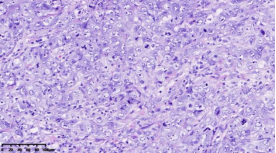

在本项研究中,研究人员利用基本的组织形态学方法及免疫组织化学法对TNBC进行分型:腔面雄激素受体型(LAR)(图1A),免疫调节型(IM)(图1B),基底样免疫抑制型(BLIS)(图1C),间充质型(MES)(图1D)。评价各亚型临床病理参数(如发病年龄、肿物大小、淋巴结转移等),组织形态学(肿物中央瘢痕形成、浸润模式、肿瘤间质浸润淋巴细胞、细胞排列方式、细胞核形态、核分裂计数、间叶化生等)以及免疫表型(p53、Rb、PD-L1、MMR等),结果显示:1.TNBC分型的临床病理、组织形态学和免疫表型特征不尽相同,有望成为复杂的基因表达谱分析的替代选择,为TNBC的分型治疗及靶向治疗提供理论依据;2.生物标记物 PD-L1作为重要的生物学指标,对个体化治疗及免疫治疗有重要的临床指导价值;3.乳腺癌中dMMR作为一个低频发生事件,不太可能作为免疫治疗有效性的评估手段。该成果发表在Virchows Archiv期刊,题目为“Subclassifying Triple-Negative Breast Cancers and Its Potential Clinical Utility”。文章DOI为:10.1007/s00428-022-03329-0。

图1. 基于组织形态学及免疫组织化学标记物的TNBC分型